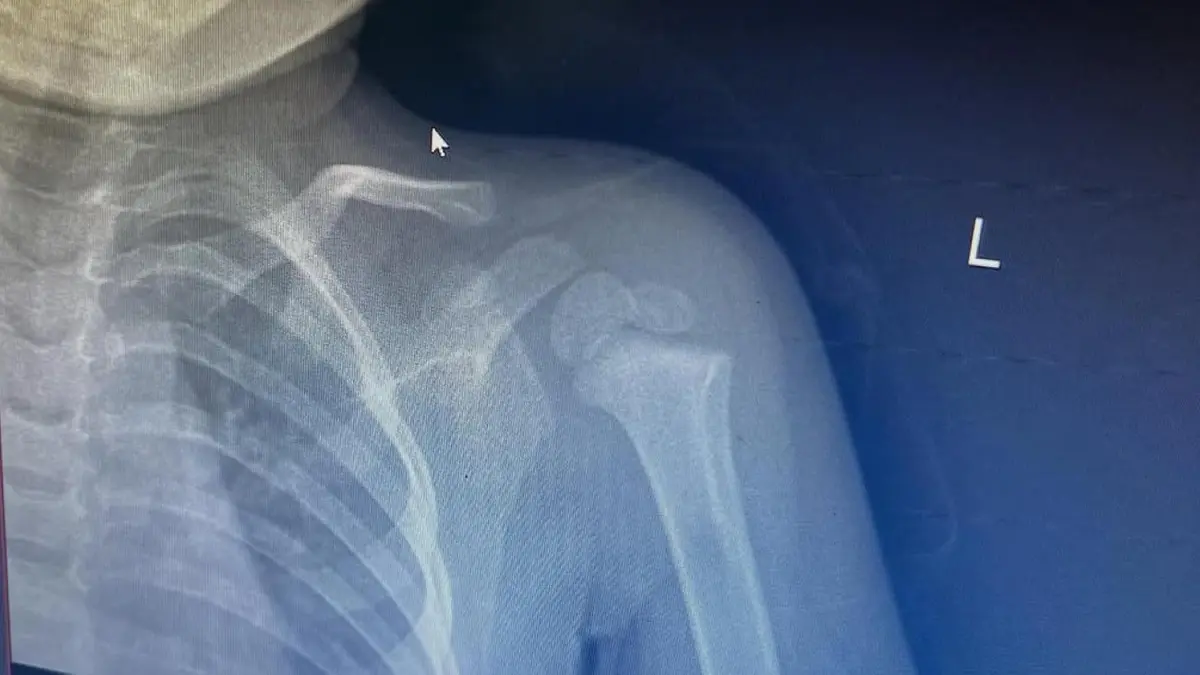

Рентген пострадавшего ребенка

Рентген пострадавшего Фото: instagram.com/_sssaparovaa_

Сегодня мы писали, что в Сети появилось видео, где подросток, вероятно, ударил о землю двухлетнего ребенка - пострадавший сломал руку. Мать малыша рассказала подробности.